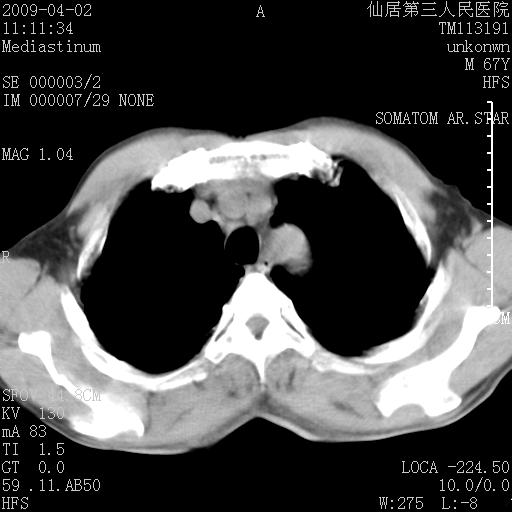

患者老年男性,乏力畏寒来诊,摄胸片示右下肺感染性病变,抗炎两周后复查胸片,无好转有进展。

后做ct平扫表现如下:

病灶呈蜂窝征,纵隔多个淋巴结肿大;肺泡癌需考虑

我认为普通的感染应该可以除外,间质性肺炎可能性较大,但如何解释纵膈的淋巴结肿大呢